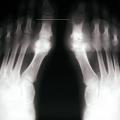

La forme pseudorhumatoïde est rare (5 %), simulant une polyarthrite rhumatoïde (diagnostic différentiel), avec parfois des signes systémiques d’inflammation (élévation de la vitesse de sédimentation et de la CRP). Le diagnostic repose sur la mise en évidence des cristaux de PPC. La radio peut mettre en évidence des calcifications des cartilages articulaires (fig. 6) et des fibrocartilages (fig. 7, 8, 9 et 10). L’échographie (plus sensible) peut mettre en évidence des dépôts de PPC, qui apparaissent comme une fine bande hyperéchogène au sein des cartilages hyalins et comme des points scintillants dans les fibrocartilages ou dans la membrane synoviale. Dans l’arthrite chronique à PPC, lespossibilités thérapeutiques sont, par ordre de préférence : colchicine (de 0,5 à 1 mg/j), petites doses de cortisone, parfois les AINS per os (mais leur prescription est souvent limitée par les comorbidités chez les patients âgés), méthotrexate et l’hydroxychloroquine. Il n’y a pas aujourd’hui de traitement « de fond », mais des molécules sont à l’étude.